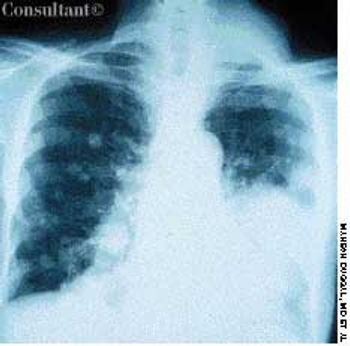

An 85-year-old man was admitted to the hospital with acough and shortness of breath of 1 week’s duration anda fever and increased sputum production for 2 days. Hishistory included renal cell carcinoma and metastatic renalcancer for 2 years. The patient had smoked cigarettesfor 30 years. He had lost 30 lb during the last few months.A chest film revealed pneumonia of the right lowerlobe. Metastatic nodules were noted on the scalp; extensivelung, bone, and brain metastases also were found.